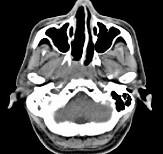

男,52岁,血涕二月余,CT如图所示,最可能的诊断为()A.鼻咽癌B.咽旁混合瘤C.咽部神经纤维瘤D.小涎液腺瘤E.咽旁脓肿

问题 男,52岁,血涕二月余,CT如图所示,最可能的诊断为()

选项 A.鼻咽癌 B.咽旁混合瘤 C.咽部神经纤维瘤 D.小涎液腺瘤 E.咽旁脓肿

答案 A